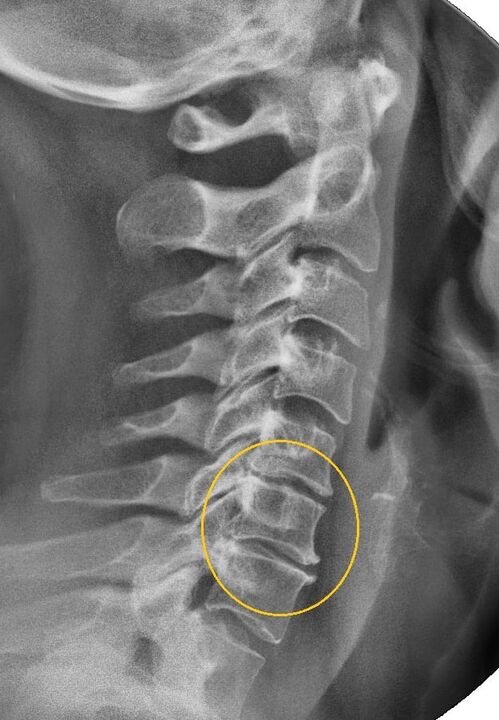

The most informative diagnostic procedure is radiography.Grade 1 pathologies correspond to radiological stage 1 or 2.The resulting images show the typical signs of the disease.

| X-ray stages of 1st degree cervical osteochondrosis | Characteristic signs |

|---|---|

| Section 1 | Minor changes in the curvature of the spine in the cervical region, affecting one or more segments |

| Section 2 | Slight thickening of intervertebral discs, deformation of uncinate processes, straightening of lordosis, minor growth of bone structures |